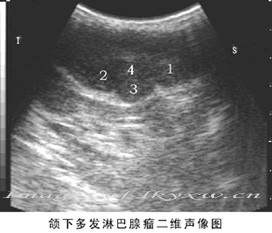

涎腺肿瘤的检查诊断